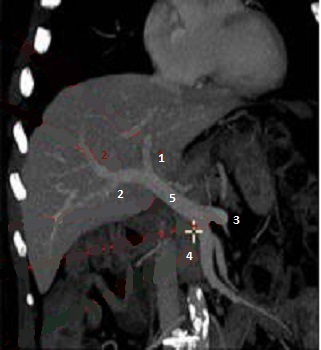

Systeme

artere hepatique ( Image TDM avec contrast en

coupe frontale , phase arterielle ): 1 Artere

hepatique gauche , branche de artere gastrique

- 2 Artere hepatique moyenne , branche de

tronc coeliaque -3 Artere hepatique

droit , branche de artere mesenterique superieure -

4 Artere mesenterique superieure - 5

Tronc coeliaque |

Systeme de veine porte (

Image TDM avec contrast en coupe frontale , phase

veineuse ) : 1- Branche porte gauche -2

Branche porte droit - 3 Veine splenique -4

Veine mesenterique superieure - 5 Veine porte

. |